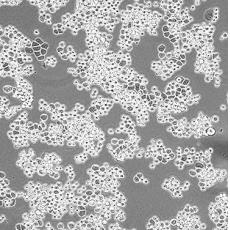

產(chǎn)品名稱 MDA-MB-453

中文名稱 人乳腺癌細胞

組織來源 乳腺腺癌;胸腔積液轉移;女性

生長特性 adherent

形態(tài)特征 epithelial

細胞描述 該細胞系由CailleauR在1976年從一名48歲的患有轉移性乳腺癌的白人女性的心包滲出液中分離建立的。該細胞表達FGF的受體。